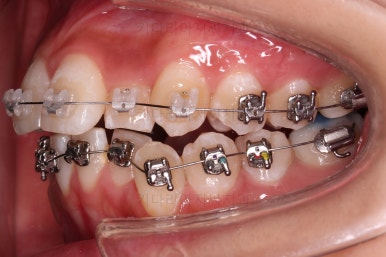

교정시작 3개월째입니다.

비발치로 가지런하게만 목표로 한다면 거의 다 끝나가네요. 효율적인 메카닉스와 술식으로 치료과정을 매우 빠르게 진행했어요.

지금쯤 다시 발치와 비발치에 대해서 말씀을 나눕니다.

각각의 장단점, 목표로 하는 바 등을 말씀 나누고 현재의 입매에서 옆라이니 좀 더 스트레이트하게 떨어지는 라인을 원하셔서 발치교정으로 넘어가기로 결정했습니다.

적절한 위치의 치아를 발치하고요.

이 뽑은 공간을 닫아주며 앞니를 뒤로 넣어줘요.

반복적으로 당겨주며 교합, 중앙선, 기울기, 입매 등을 맞춰 나갑니다.